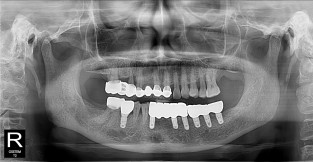

• 2

전체어금니

치료기간 : 2021-11-08 ~ 2022-12-22

1. 상기 x-ray 이미지 모두 동일한 해당 의료기관에서 진료한 환자입니다.

2. 상기 x-ray 이미지 모두 동일 인물의 것입니다.

3. 치료 전 이미지는 2021-11-08에 촬영했으며, 치료 후 이미지는 2022-12-22에 촬영하였습니다.

4. 상기 x-ray 이미지 모두 동일 조건에서 환자분의 동의를 받아촬영되었습니다.

* 임플란트 시술은 환자분의 상태(고혈압, 당뇨 등)에 따라 부작용이 있을 수 있으니, 반드시 전문의와 상담이 필요합니다.

* 임플란트 수술 부작용

: 수술 후 출혈, 교합, 통증, 붓기, 염증 등의 문제점이 발생할 수 있습니다.)